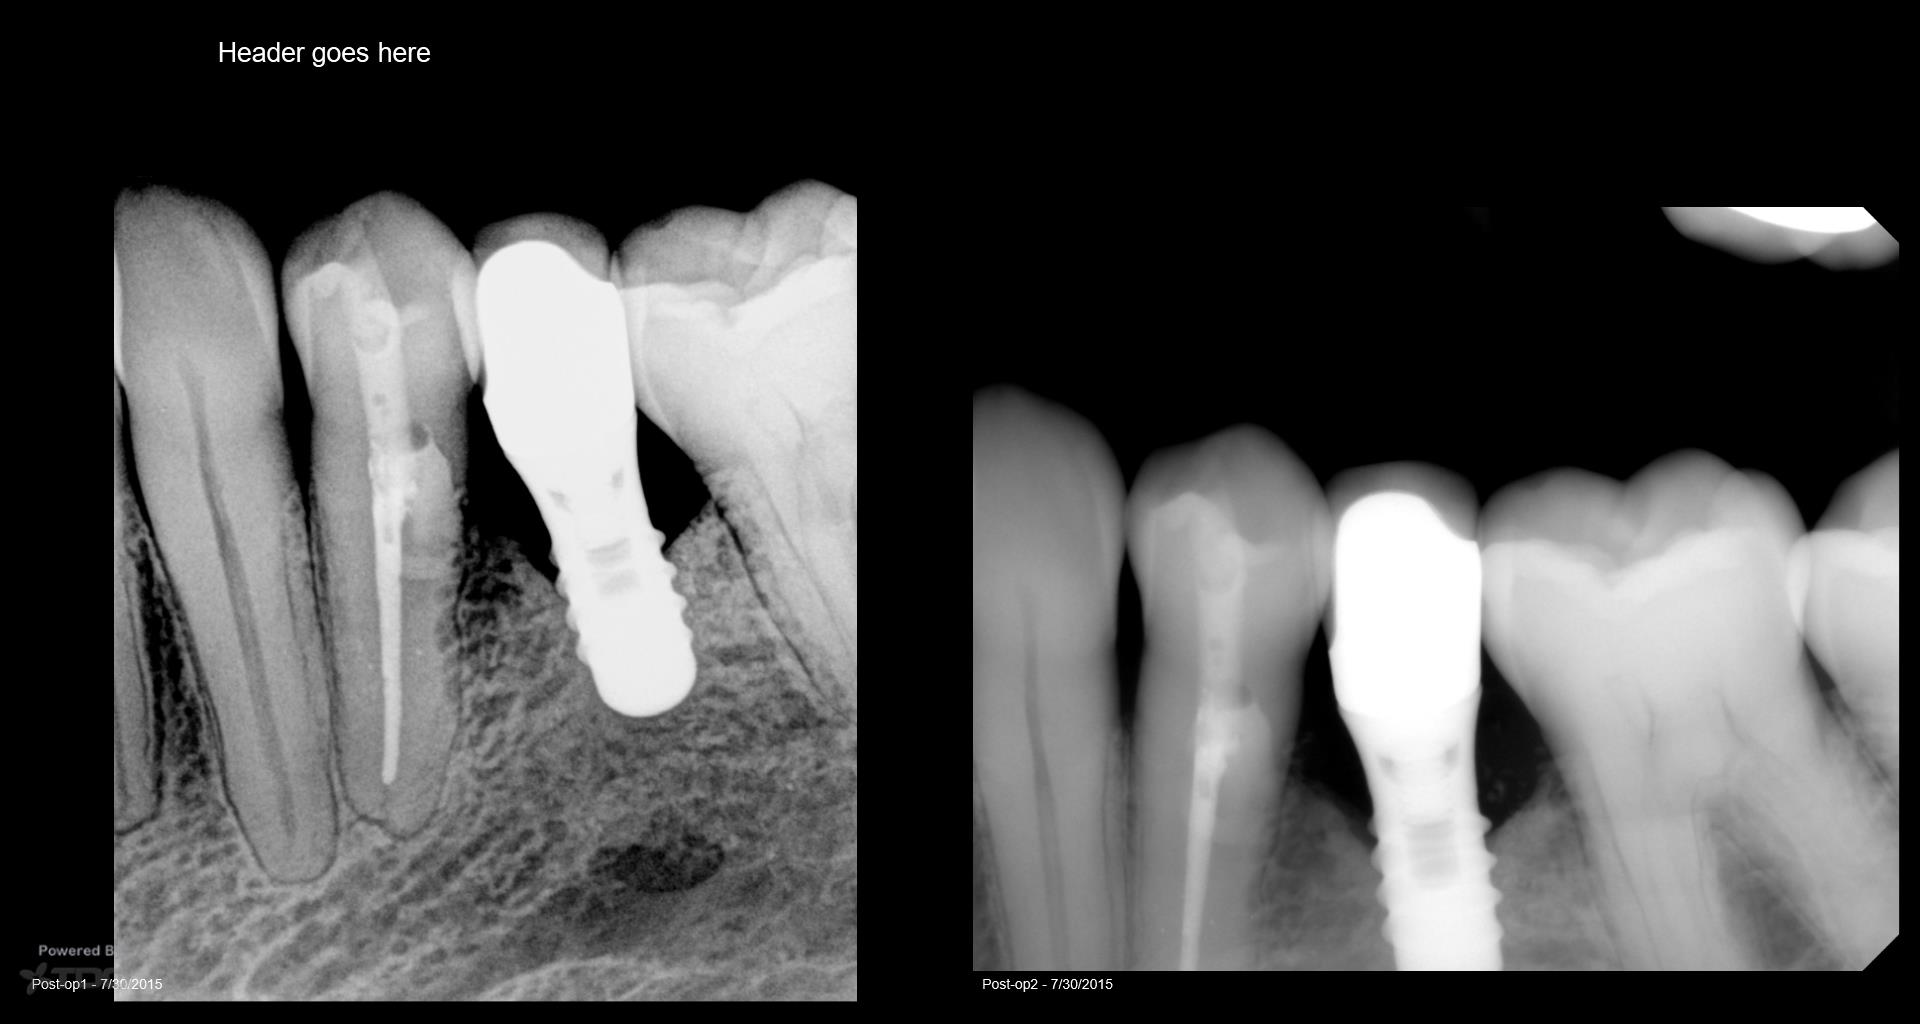

I struggled with the composite. I think I could do it better today but at least the repair seems to be holding. The defect went from line angle to line angle–the whole buccal face of the tooth. . gbc